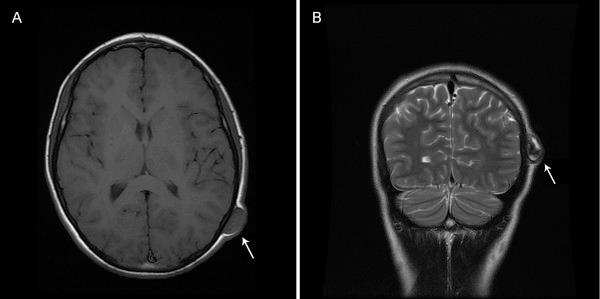

We report the case of a 14-year-old Caucasian boy presented with a painless non-pulsatile scalp mass that developed rapidly after minor blunt head trauma. The scalp mass was excised six months after the trauma. A pathologic diagnosis of a thrombosed true aneurysm was made. Our patient has had no recurrence of the mass at 15 months follow-up.

我们报告一例14岁白种男孩,因轻微钝性头部外伤后迅速出现无痛性非搏动性头皮肿块。外伤6个月后切除头皮肿块。病理诊断为血栓形成的真性动脉瘤。在15个月的随访中,我们的患者肿块未复发。